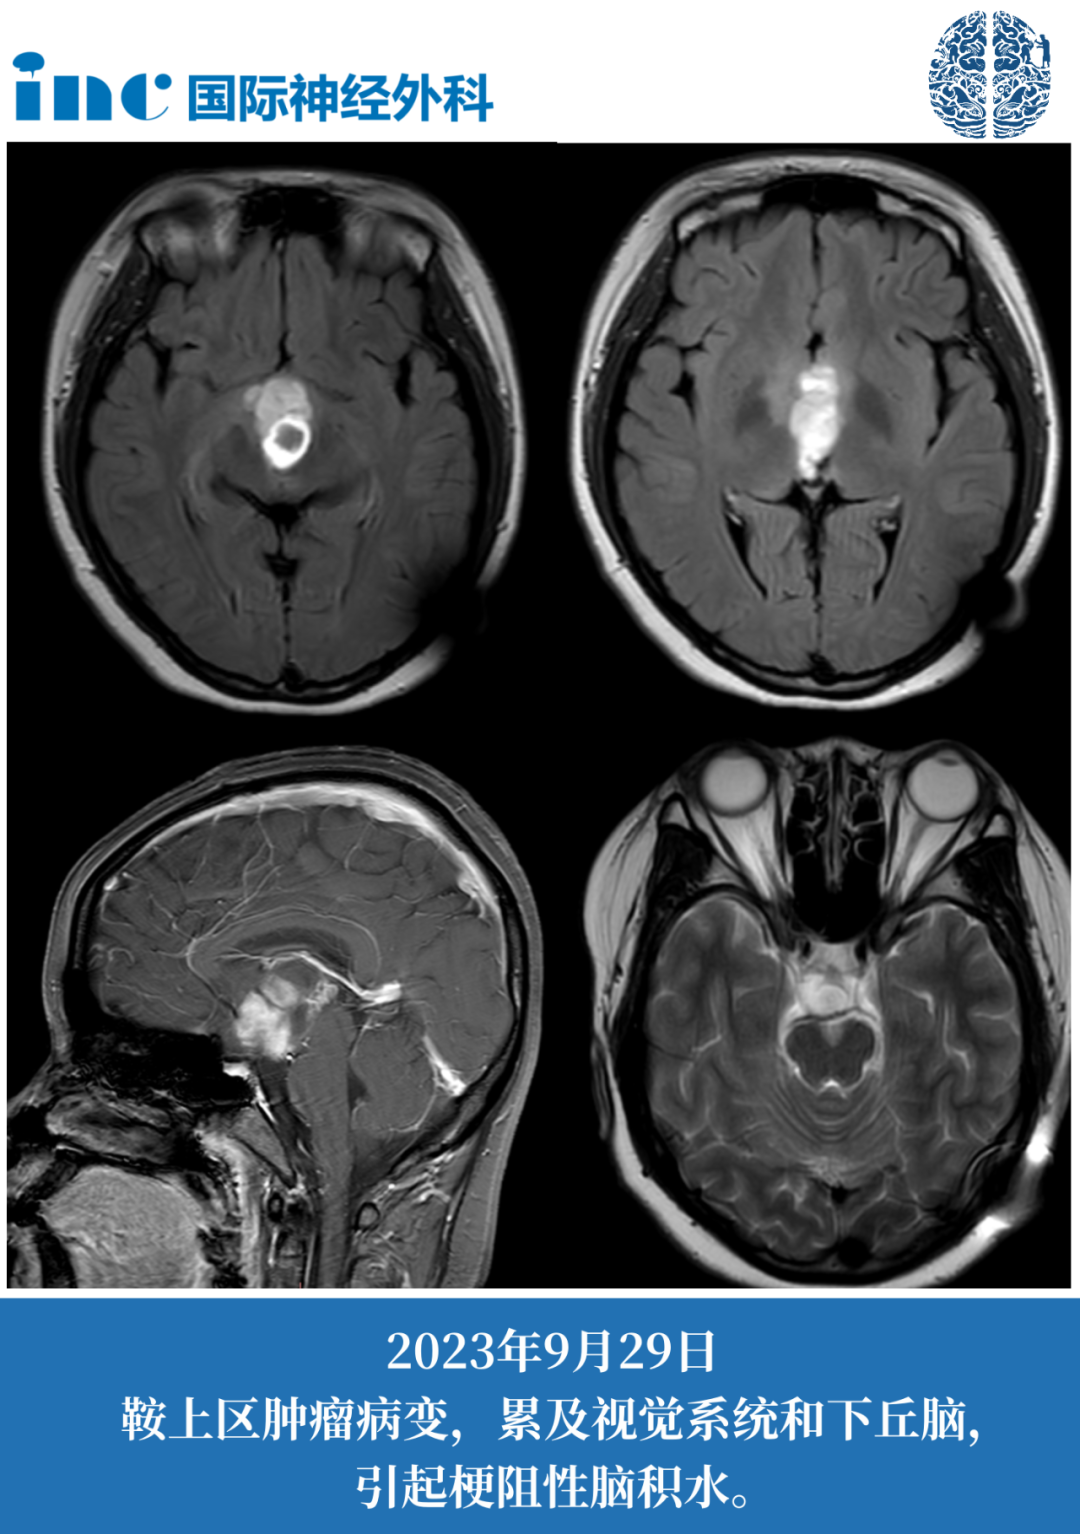

潜在的病灶是鞍上区有增强的肿瘤病变,累及视觉系统和下丘脑,引起梗阻性脑积水。CT扫描显示由于脑室间孔阻塞需要双额分流导管。它很可能是一种低级别胶质瘤,但也可能是其他类型实体肿瘤。